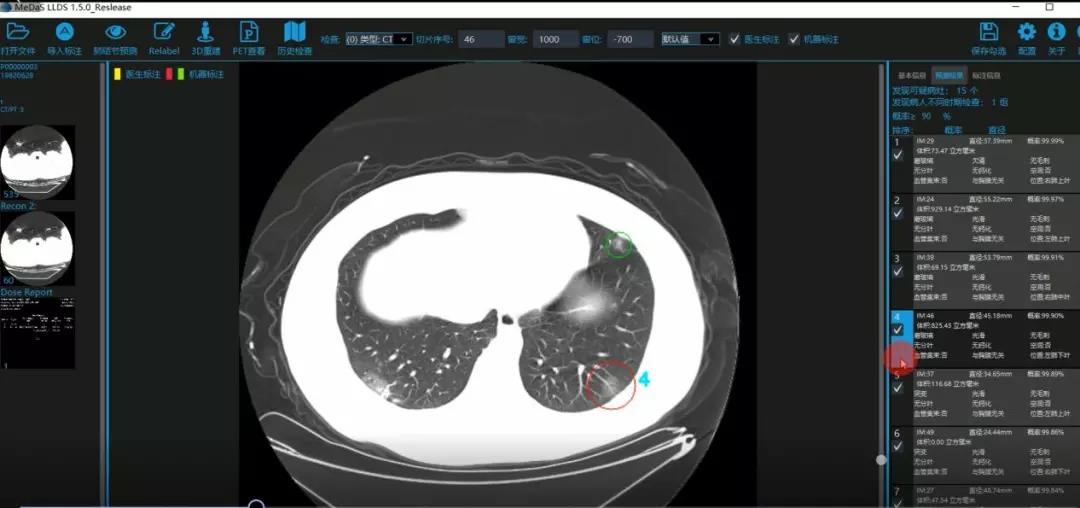

对应新冠肺炎CT病灶检测效果

令人欣喜的是,通过对实际门诊数据排查测试,该模型可以减轻医护人员近80%的工作量,新冠肺炎患者的检测召回率超过95%。目前,模型系统正在进行最后的调试工作,很快投入到“战疫”一线,缓解医护人员紧缺、确诊检测工作耗时较长等问题,减少医护人员的工作时间和劳动强度,提高工作效率。